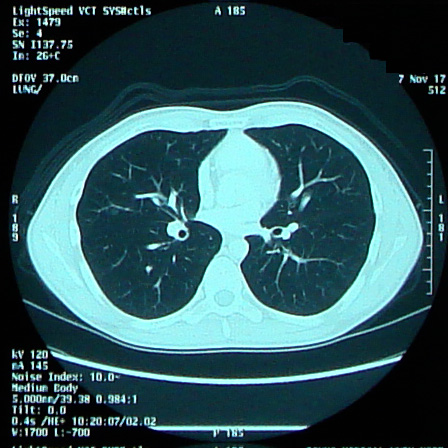

HN:ごう 年齢:47 性別:男性 誕生年:1973年 自己紹介: 2001年10月 精巣腫瘍で右睾丸摘出 2006年8月 後腹膜リンパ節に転移でBEPを3クール実施 2006年11月 退院 メールはこちらまで(@は変換してくださいね)